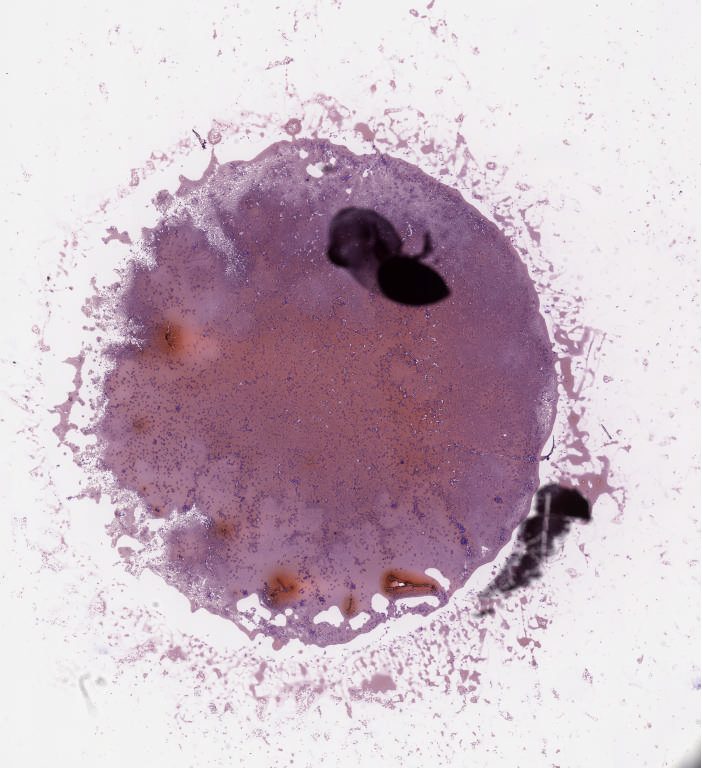

Case6 dq.svs

31872

x

34880

@

40X